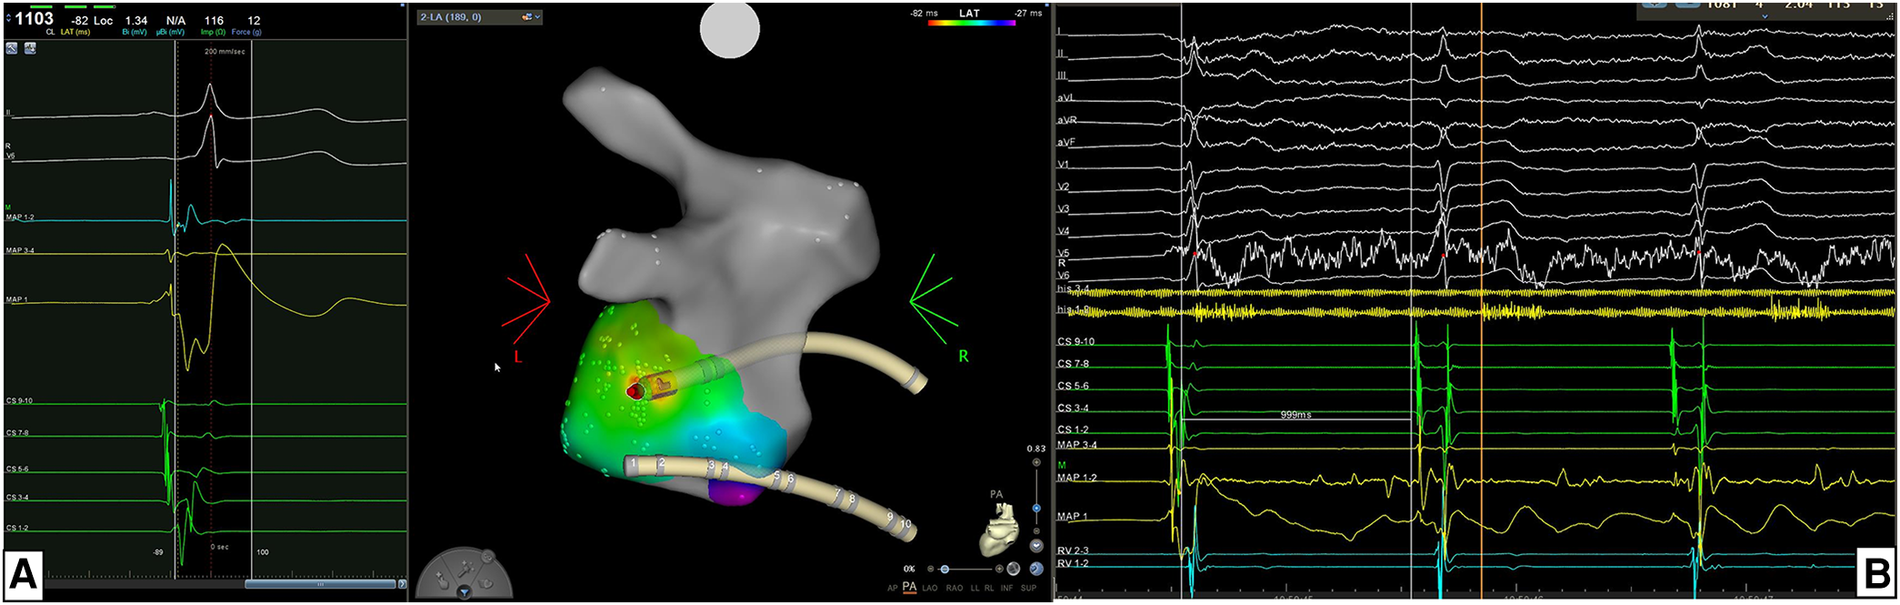

Figure 2

(A) Example of the location of accessory pathway (AP) being in the left postero-lateral region. For mapping and ablation of this left-sided AP an retro-aortic approach was performed. Atrial activation map was obtained during sinus rhythm with ventricular pre-excitation and a unipolar EGM with qS morphology and a continuous A-V EGM were recorded at the ablation point automatically marked by the system. (B) The acute success was 100% acutely with time to effect (TTE) was 2.0 s. In this case the AP block was achieved with just a single RF application.